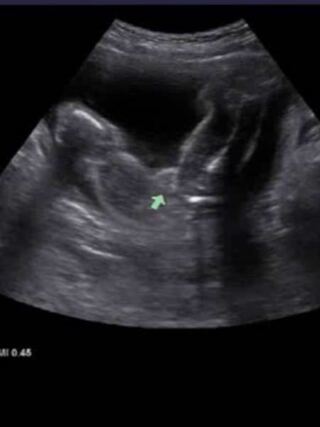

妊婦ばなし 胎児の女性器エコー 41歳で5人目無事出産 年の差5人兄弟ママ 保護猫おはぎはてんかん治療中

写真多数 週数別女の子のエコーの見分け方 性別判定 こそだて情報局 こそだて情報局

最高のイラスト画像 Hd限定女の子 エコー 葉っぱ